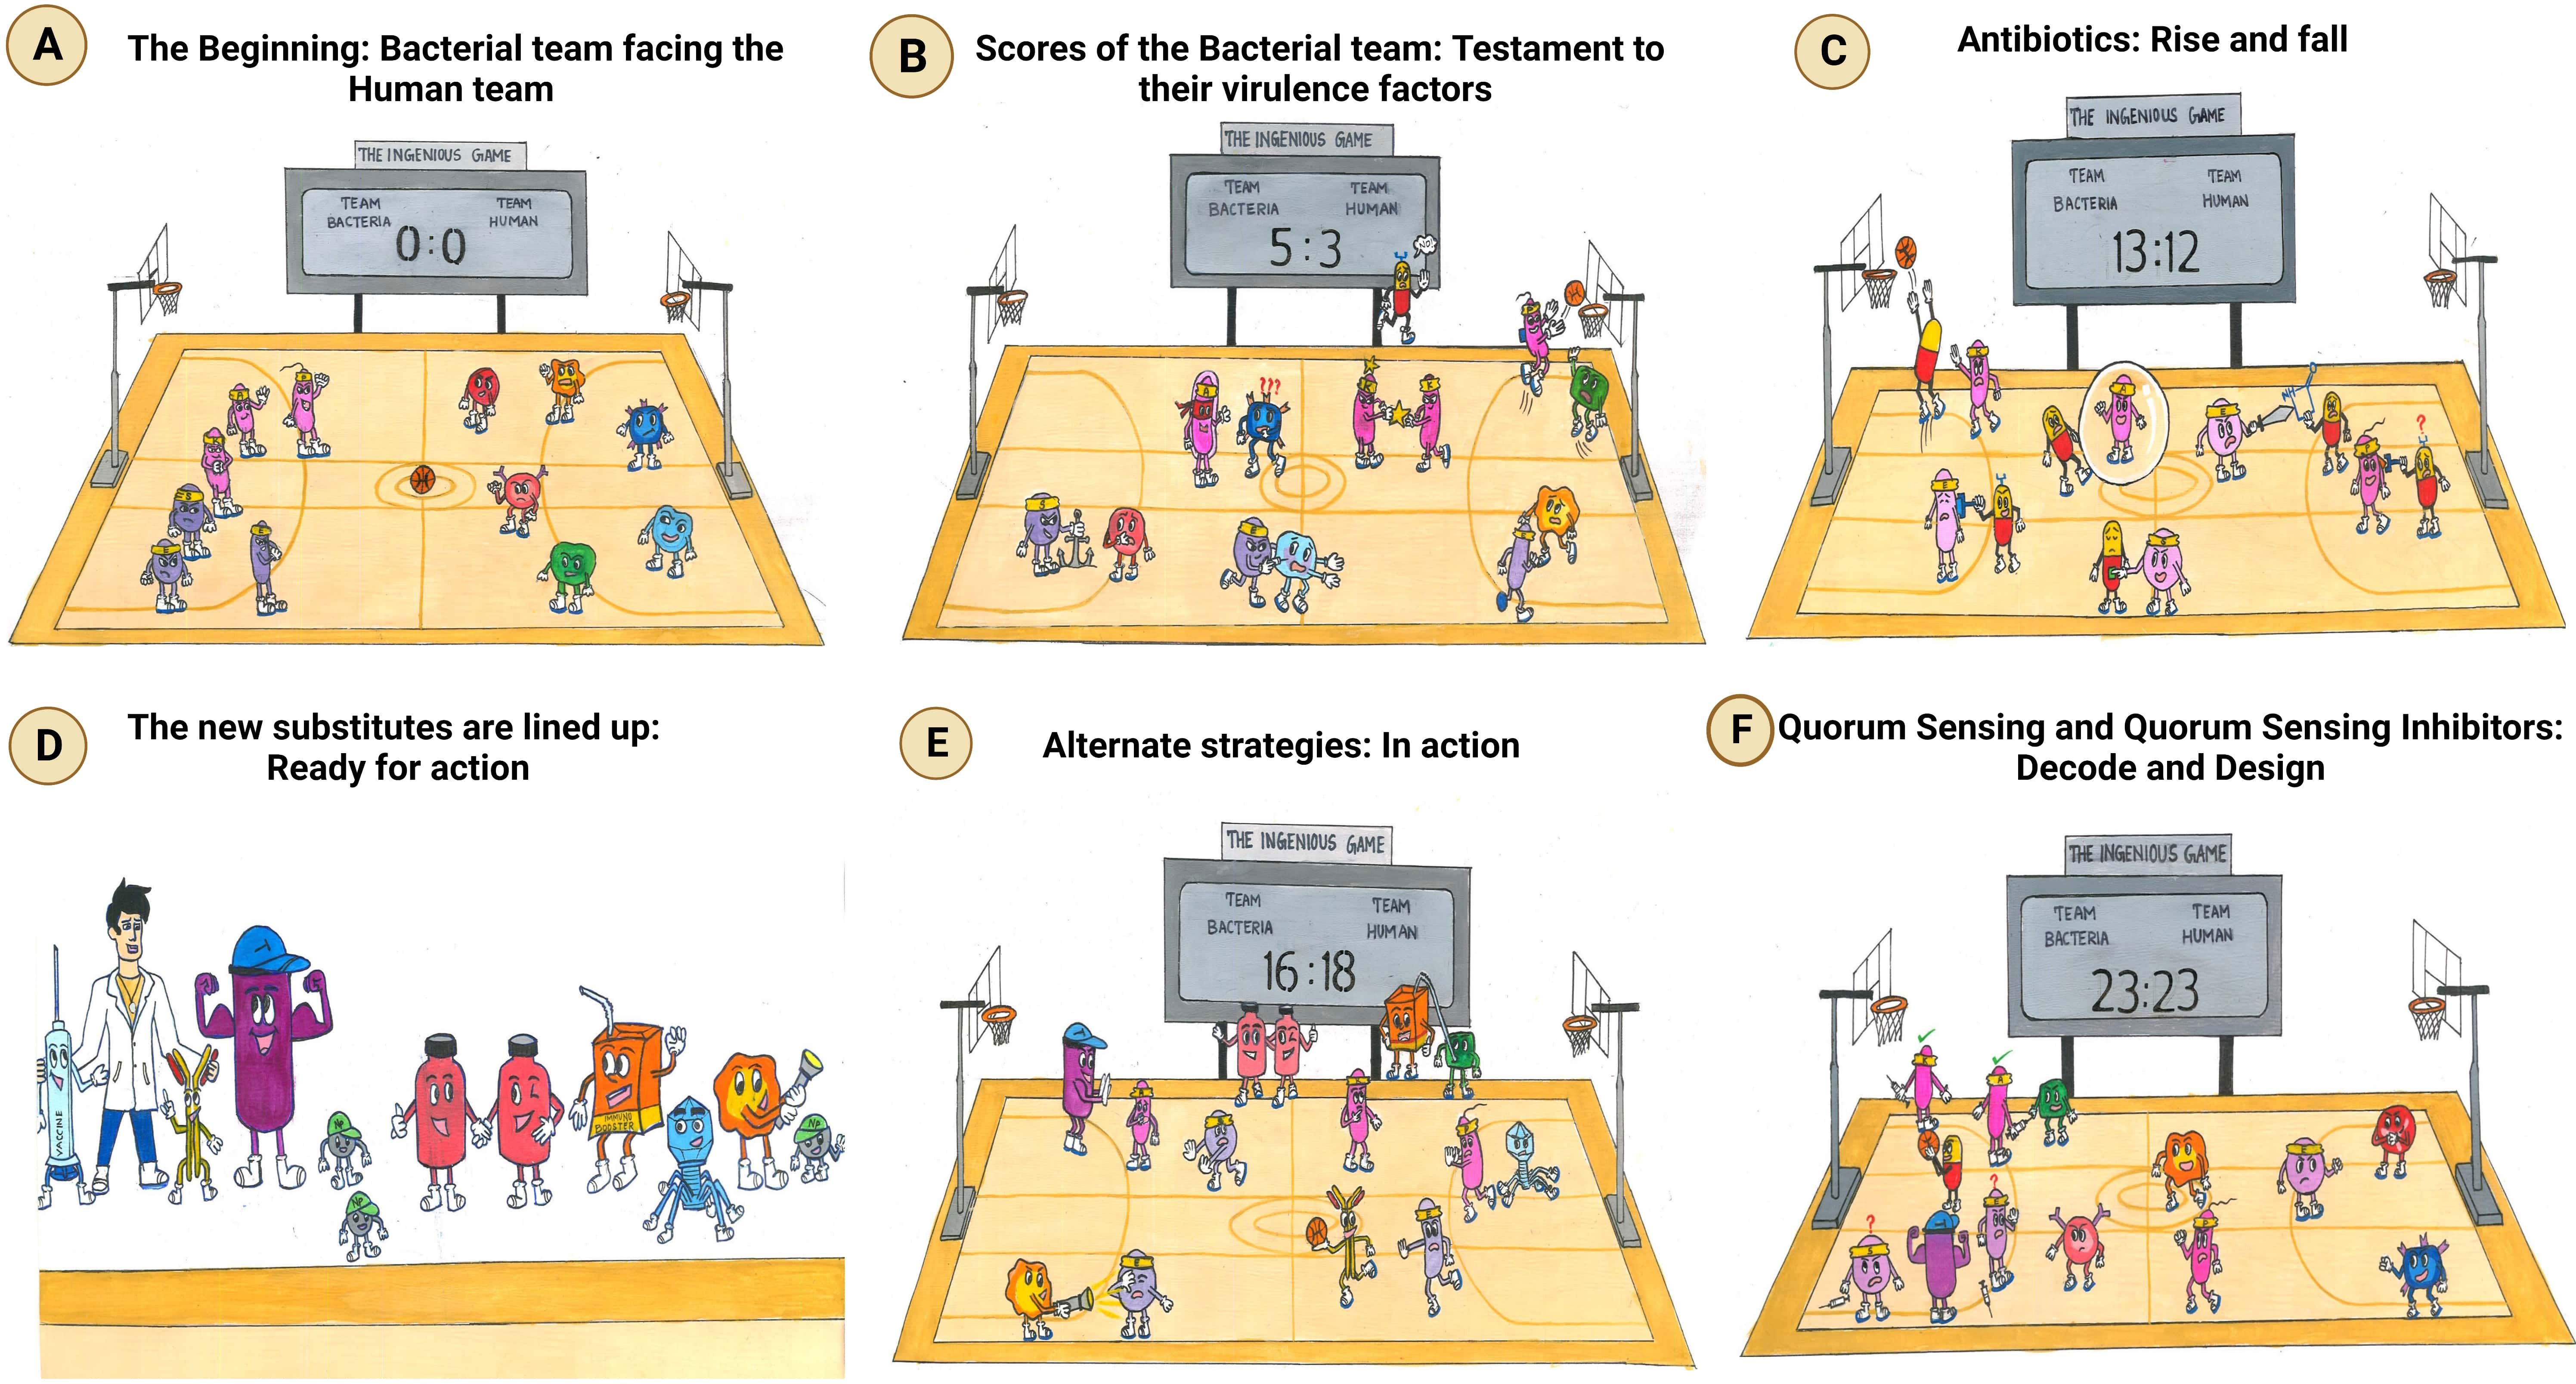

Frontiers Revisiting ESKAPE Pathogens: virulence, resistance, and combating strategies focusing on quorum sensing